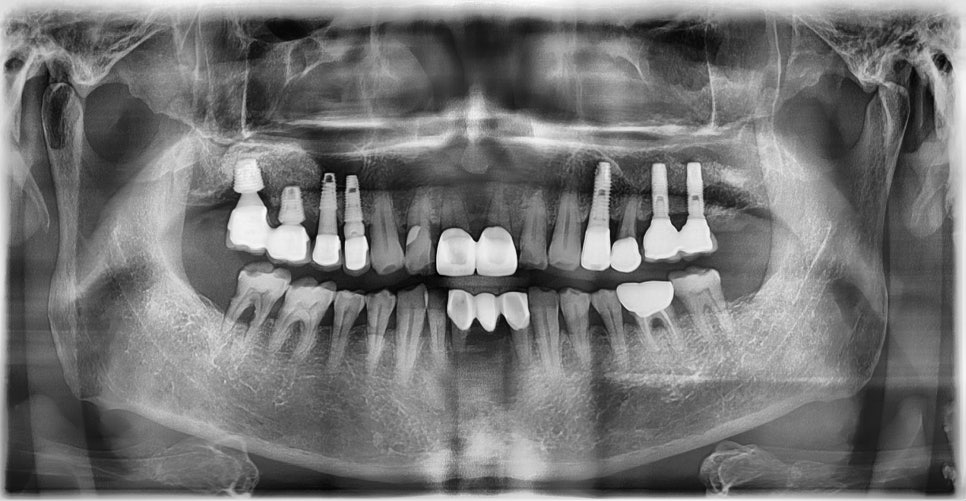

위 케이스들처럼 전신질환이 있는 경우에도 충분한 상담과 준비 과정을 거쳐 안전하게 수술을 마쳤으며, 환자분들도 만족스러운 치료 결과를 얻으셨습니다. 당뇨병을 앓고 계신다 하더라도 혈당이 잘 관리되고 있다면 충분히 안전하게 임플란트 치료를 진행할 수 있습니다. 고혈압 역시 사전에 충분한 혈압 조절과 철저한 준비가 이루어진다면 임플란트 수술 역시 안전하게 진행할 수 있습니다.

최근 연구에 따르면, 고혈압이나 당뇨병을 가진 환자도 질환이 적절히 조절되고 있을 경우 임플란트 성공률이 건강한 사람들과 크게 다르지 않다는 결과가 발표되고 있습니다. 예방적 항생제 투여, 정밀한 사전 검진, 최신 디지털 장비를 활용한 수술 계획 수립 등 의료 기술의 발전으로 인해 만성 전신질환이 있는 환자도 보다 안전하게 임플란트 치료를 받을 수 있는 환경이 조성되고 있습니다. 결국 중요한 것은 질환 자체보다는 그 관리 상태와 의료진의 경험, 그리고 환자와 의료진 간의 충분한 소통입니다. 단순히 ‘가능 여부’를 판단하기보다, 본인의 건강 상태에 맞춘 맞춤형 치료가 가능한지 전문의와 충분히 상담해보시기 바랍니다.